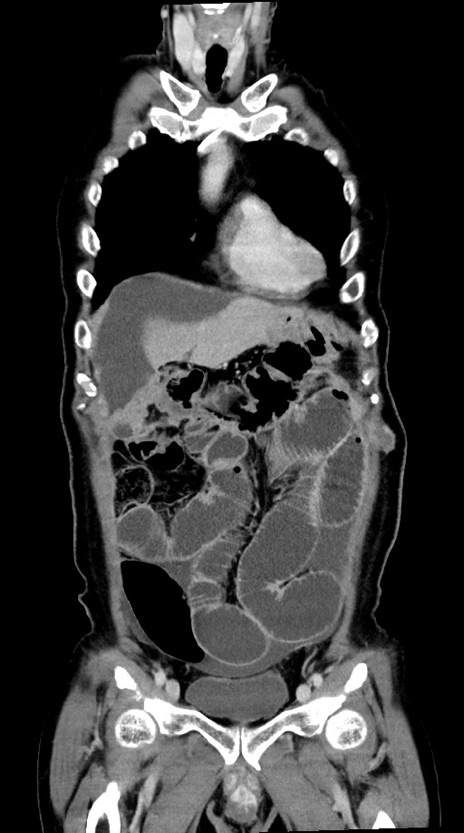

症例28(冠状断像)

【症例】60歳代男性

【主訴】嘔吐

【現病歴】胃癌にて胃全摘後。食思不振が悪化し、夜中に嘔吐することがある。

【既往歴】胃癌、胃全摘、脾摘、胆摘後

【データ】WBC 5900、CRP 10.56